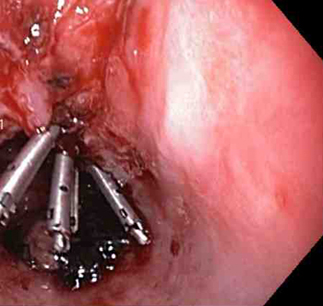

A mechanical method (e.g., clips) with or without adrenaline (epinephrine). In practice, both through-the-scope clips (TTSC) and over-the-scope clips are options depending on availability and expertise. However, for MWT, TTSC usually suffice.[Figure caption and citation for the preceding image starts]: Mallory Weiss tear after application of through-the-scope clip results in haemostasisFrom the personal collection of Douglas Adler; used with permission [Citation ends].

Through-the-scope clips (TTSC), alone or in combination with adrenaline injection to clear the visual field

TTSC are widely available, have a robust evidence base and are usually sufficient to control bleeding in MWT.

TTSC use is as safe and effective as other methods for controlling actively bleeding lesions.[76][77][78][Figure caption and citation for the preceding image starts]: Mallory Weiss tear after application of through-the-scope clip results in haemostasisFrom the personal collection of Douglas Adler; used with permission [Citation ends].